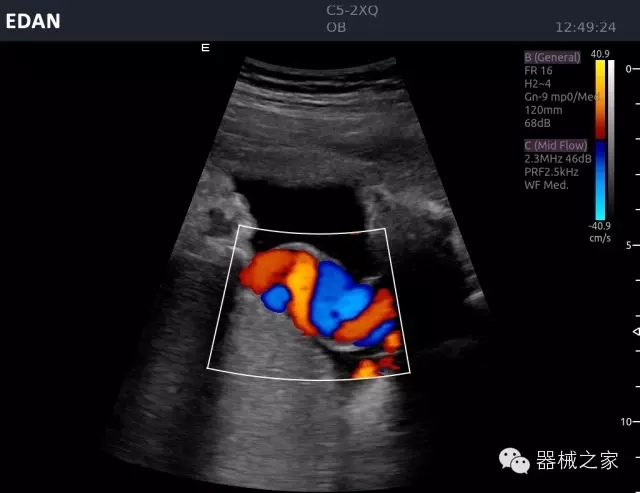

品牌:理邦儀器(EDAN)

公司簡介:

理邦立足健康產(chǎn)業(yè),以全球化的視野、持續(xù)的創(chuàng)新和卓越的服務(wù),成為國內(nèi)規(guī)模最大的醫(yī)療健康產(chǎn)品、解決方案和服務(wù)提供商之一。涵蓋病人監(jiān)護(hù)、心電產(chǎn)品、超聲影像、婦幼健康、體外診斷、智慧健康六大業(yè)務(wù)板塊。在中國,理邦輻射全國市場的服務(wù)網(wǎng)絡(luò)已為超過17000家醫(yī)療機(jī)構(gòu)提供了創(chuàng)新型、高品質(zhì)的產(chǎn)品和服務(wù)。在全球設(shè)立五大研發(fā)中心、14個(gè)子公司,產(chǎn)品遠(yuǎn)銷150多個(gè)國家和地區(qū)。全球醫(yī)療專家信賴?yán)戆钔黄菩缘尼t(yī)療技術(shù)和出色的客戶服務(wù)。(理邦儀器SHE:300206)

官方網(wǎng)站:www.edan.com.cn

經(jīng)典產(chǎn)品:Acclarix AX8

臨床圖片賞析

睪丸低速血流

臍帶血流

頸動(dòng)脈頻譜

產(chǎn)品特點(diǎn)

·新視界、高效能、新體驗(yàn);

·別具匠心的獨(dú)特設(shè)計(jì)、創(chuàng)新工作流、強(qiáng)大的功能組合以滿足POC圖像的需求;

·15英寸高分辨率顯示器;

·10.1英寸防指紋觸摸屏;

·獨(dú)一無二的觸控式軌跡球;

·超聲模塊的便攜式設(shè)計(jì);

·128物理通道;

·UPS持續(xù)供電;

多項(xiàng)前沿圖像技術(shù)

·復(fù)合成像 波束合成 頻率復(fù)合 噪聲抑制等;

穿刺針增強(qiáng)技術(shù)

·顯著增強(qiáng)針體 清晰識(shí)別結(jié)構(gòu)、位置等比鄰關(guān)系;

多種成像模式

·梯形成像 寬景成像 3D成像 特征成像等;

CFDA注冊證編號(hào)

·粵械注準(zhǔn)20152230912